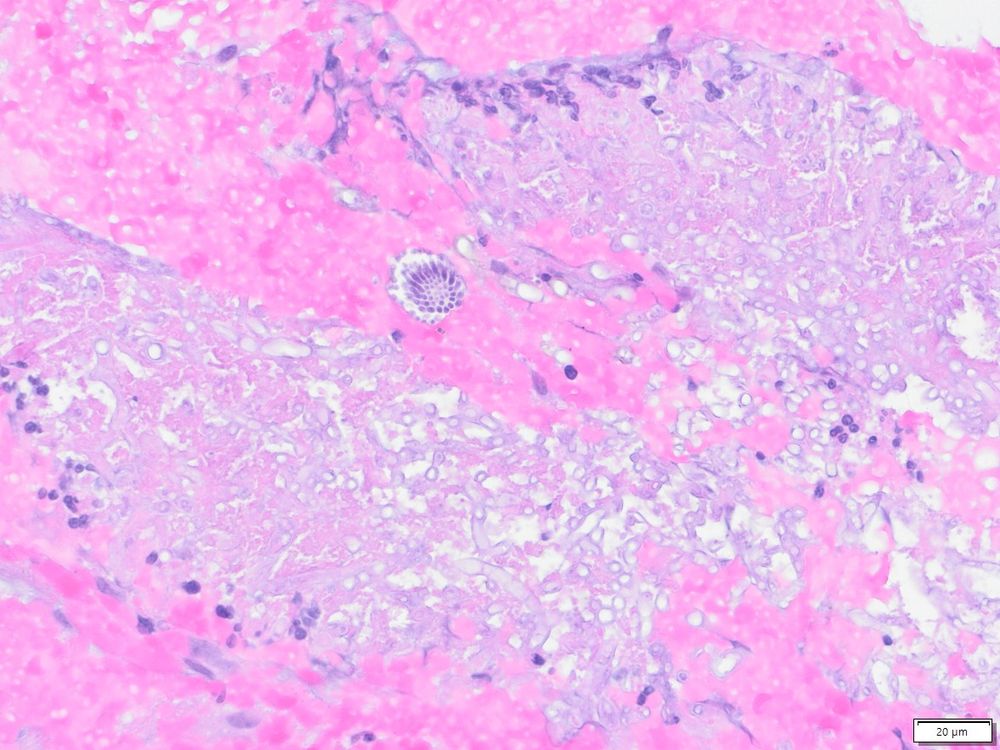

Here is the kind of fungi I find at work complete with conidiophores in a bronchial mucosa biopsy courtesy by @jgottlieb.bsky.social.

Not so happy but treatable!

#PathSky